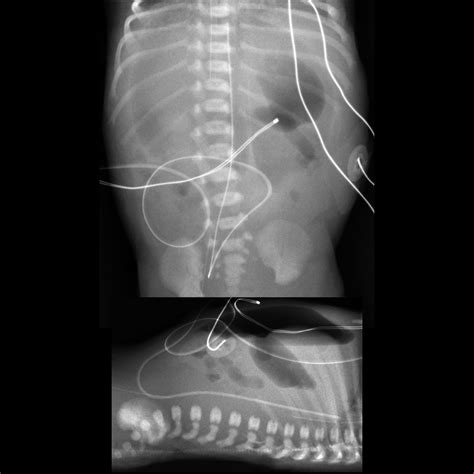

• Imaging Tests: In some cases, imaging tests such as X-rays or ultrasounds may be ordered to visualize the intestines and identify any blockages or abnormalities.